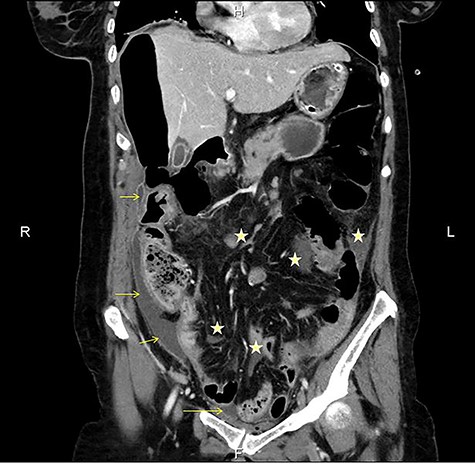

The patient was afebrile but hemodynamically unstable, with 115 bpm and a systolic pressure of 80 mmHg on presentation. Clinical examination revealed abdominal distension, diminished bowel sounds and severe tenderness with peritoneal signs in all of the abdominal quadrants. Her laboratory blood examination showed elevated number of neutrophils (7.77 K/μl), elevated C-reactive protein value (82.46 mg/dl) and decreased Na+ (119 mEq/l). After initial resuscitation, a computed tomography (CT) scan was performed. It showed free abdominal air and fluid in the peritoneal cavity, indicating an intestinal perforation (Figs 1–3).

CT multiplanar reconstruction (upper level, supine position) shows free air in continuity with intraluminal (duodenum) air. Notice the presence of free fluid in mesenteric pouches (stars), as well as encapsulated in the right paracolic gutter (arrows) and Douglas space (long arrow).